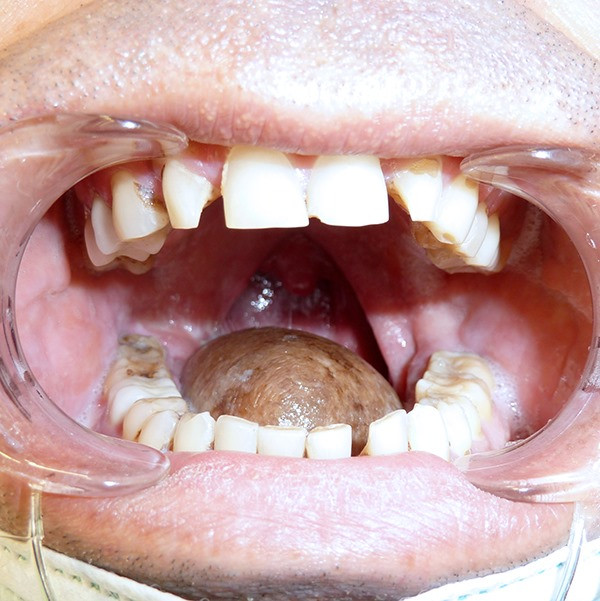

Պացիենտը 50 տարեկան տղամարդ էր, որի մոտ հայտնաբերվել էր լեզվի տարածված քաղցկեղ: Հիվանդության կապակցությամբ կատարվել է լեզվի ամբողջական հեռացում` ուռուցքի հետ միասին, որից հետո լեզուն ամբողջությամբ վերականգնվել է կրծքավանդակի կողմնային մակերեսից ձևավորված հատուկ մաշկամկանային անոթավորված և նյարդավորված լաթով:

Առաջին անգամ հայաստանում կատարվող այս վիրահատության բացառիկությունն այն է, որ հնարավոր է եղել վերականգնել ո՛չ միայն լեզվի կառուցվածքը, այլ նաև` շարժունակությունը, ինչն իրականացվել է մաշկամկանային լաթի նյարդերը լեզվի պահպանված նյարդերին միացնելու արդյունքում: Վիրահատությունը տևել է 16 ժամ:

Վիրահատության վիրաբուժական թիմում ընդգրկված էին գլխի և պարանոցի ուռուցքաբան (Արամ Բադալյան), միկրովիրաբույժներ (Իրինա Րեբրիկովա, Ալեքսանդր Մորդովսկի) և դիմածնոտային վիրաբույժներ (Արսեն Շալջյան, Կարեն Վարդանյան): Նրանց առջև դրված էր երկու կարևոր խնդիր. առաջինը` հեռացնել ուռուցքն առավելագույն արմատական եղանակով, որպեսզի կանխվի կրկնությունը, և երկրորդը` վերականգնել լեզվի կառուցվածքը և ֆունկցիաները (կլման ակտը, խոսքը):